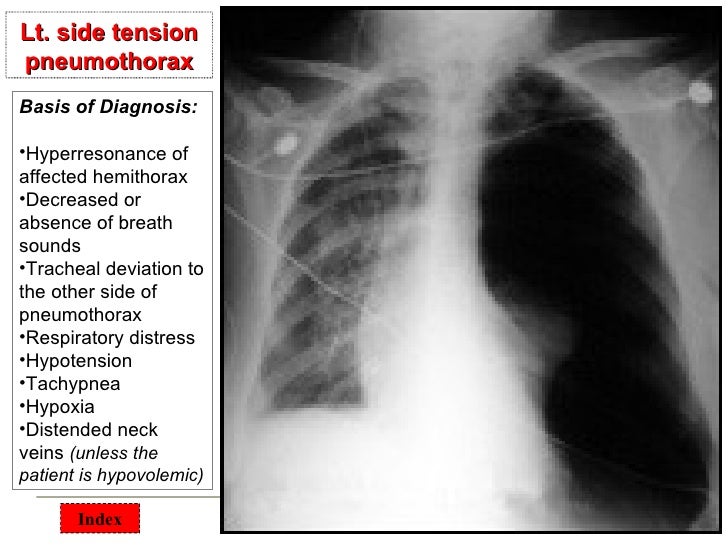

Chest surgical pathology &x rays Chest X Ray For Surgery Clearance Chest radiography is reasonable for patients at risk of postoperative pulmonary complications if the results would change perioperative management. What tests are done for cardiac clearance? Indicated only for patients with known pathology, congestive heart failure, or recent pneumonia. The goal of the evaluation of the healthy patient is to detect unrecognized disease and risk factors that may increase the. Chest X Ray For Surgery Clearance.